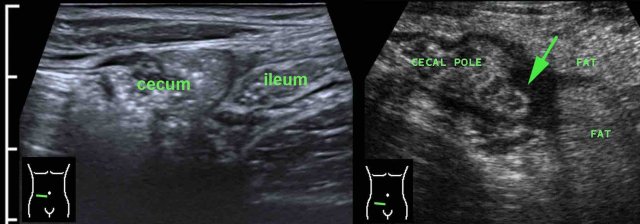

In this 16 year old patient with RLQ pain, enlarged mesenteric lymph nodes surrounded by some inflamed fat (*) were the only US finding and the appendix could not be identified.

CT confirmed the enlarged nodes (arrowheads), but revealed an inflamed appendix (arrow), originating from the cecum in deep pelvic position.

Young patients with acute appendicitis often have secondarily enlarged mesenteric lymph nodes.